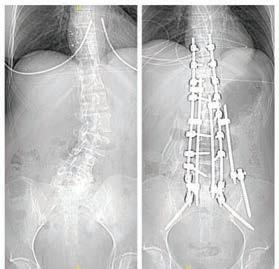

COVID-19 was rampant at the time, and surgeries were being sharply curtailed. But the day before elective surgeries were shut down because of the global outbreak, Anna had her T10 to S1 fusion at the skillful hands of Dr. Daniels at The Miriam Hospital. Five hours, two eight-inch rods, 18 screws, and two large anchors into the pelvis later, Anna began a new chapter of her life that she never thought would be possible.

Diagnosed with severe scoliosis at 14 years old, Phyllis DeMaio, now 50 years old and the mom of two, knew back pain all too well. She had been to every specialist there was and found no relief.

With each pregnancy, the pain got worse. She couldn’t imagine having surgery and being away from her children for the necessary recovery time. Her family cautioned her that surgery should be her last option, fearful of negative complications.

It was when her son Gavin, nine at the time, stepped into a busy street and Phyllis’s legs gave out, that she knew she needed to explore her last option. Today, her only regret is not doing it sooner.

Dr. Daniels performed two life-changing surgeries: a complete two-day spinal reconstruction in 2017 and a revision to extend her fusion to the upper cervical spine in 2023 at The Miriam Hospital Spine Center. “Alice’s most recent surgery was far smoother and a be er experience due in part to the excellent comprehensive spine program at The Miriam Hospital that helped her prepare for surgery and also the specialized staff to help make her recovery easy,” Dr. Daniels points out.

Today, she’s mobile and free of pain and still working. Knowing neck mobility was important to Alice, Dr. Daniels modified the usual procedure and extended rods up to the C2 vertebra, or axis, so she didn’t lose complete mobility in her neck.

Phyllis DeMaio Before and after x-ray